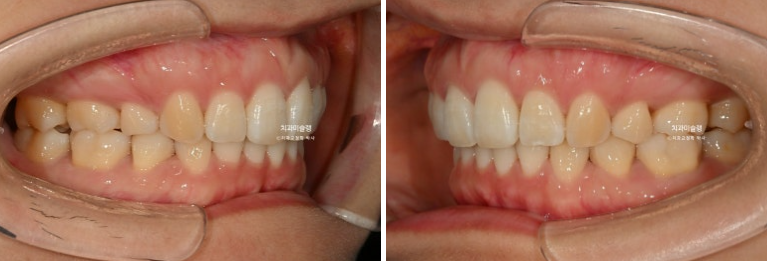

2022.11~2026.01

어금니 교합은 뜨는 곳 없이 좋습니다.

입모양과 어긋난 편평한 스마일라인에서 아랫입술과 평행한 스마일라인으로 탈바꿈

앞니 각도는 적절하며